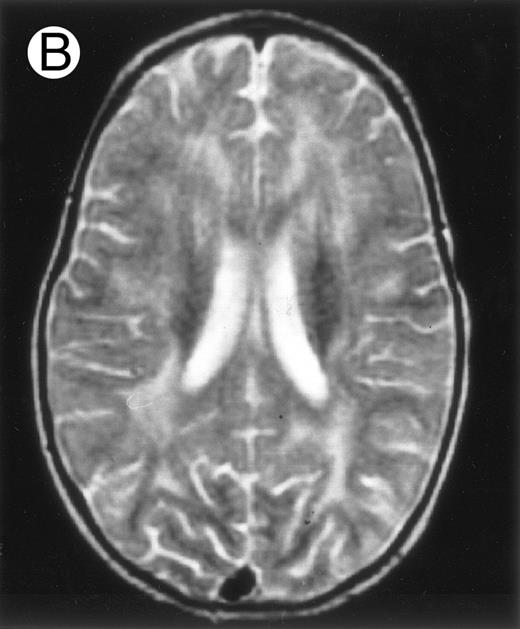

Three different aspects of brain imaging in HLH patients. (A) CT scan of a 3-month-old baby showing a large subdural effusion, several necrotic areas and hypodensities of the white matter. (B) Brain magnetic resonance of a 14-month-old boy showing large confluent areas of hypersignal in T2-weighted images. (C) Large symmetrical necrotic areas of cerebellar white matter in a 41/2-year-old girl (MRI).

Among the nine children with initial neurological symptoms, seizures were the most frequent initial symptom in the youngest patients, whereas ataxia was found in the two oldest patients (46 and 58 months old, respectively) (Table 1). All nine patients had the same CSF abnormalities as patients with meningitis only. Eight of these nine patients had a neuroradiological study performed at the time of their first neurological symptoms (Table 1). The two most frequent lesions were focal necrosis with parenchymal volume loss and atrophy (Fig 2A and C) and white matter abnormalities (Fig 2B). Several small focal lesions with hypersignal at MR imaging that enhanced after administration of gadopentate dimeglumine (or contrast on CT scan) were also observed in two cases.

Abnormalities on brain imaging appeared to roughly parallel the severity of clinical manifestations. All patients with neurological symptoms, but also half of the patients with initial meningitis, had abnormal brain imaging usually consisting of a combination of diffuse white matter abnormalities and necrotic areas with parenchymal volume loss, as previously described.8,23 In patients with isolated meningitis, however, only white matter abnormalities were detected, whereas necrotic lesions and cerebral atrophy were found in patients with neurological symptoms. These lesions progressed despite chemotherapy. Previous neuropathological studies have demonstrated infiltration by monocytes and activated lymphocytes of leptomeninges and brain parenchyma along penetrating vessels.24,25 Infiltration is associated with focal and confluent areas of myelin pallor, as well as neuronal loss, tissue necrosis, and cavitation,24,25 findings that were also demonstrated in the neuropathologic study of five patients in our series. Leukocytes infiltrating the CNS probably secrete cytokines and other neurotoxic factors, such as tumor necrosis factor-α (TNF-α), which may be responsible for the myelinic alteration observed in neurologically asymptomatic patients. Infiltrating leukocytes could also activate in parallel the numerous resident brain macrophages (the microglial cells) and astrocytes, which in turn, can secrete neurotoxic glutamate and free radicals.26